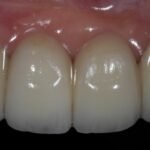

Punto Bajío Casos Clínicos Prótesis Fija sobre Implante unitario Inicio Provisional Final Prótesis Parcial Fija sobre 2 Implantes 2 Implantes Final Prótesis Bucal Removible Inicial Inicial Superior Inicial Inferior Rayos X Inicial Rayos X Inicial Frontal Final Final Superior Final Inferior Prótesis Parcial Fija/ Coronas de Circonio Sonrisa Inicial Foto Inicial Foto Inicial Inferior Foto Final Inferior Foto Final Sonrisa Final Prótesis Total Protesis Inmediatas 1 Protesis Inmediatas 2 Prótesis Removible/ Coronas Metal-Ceramica Carillas Incrustaciones Endodoncia